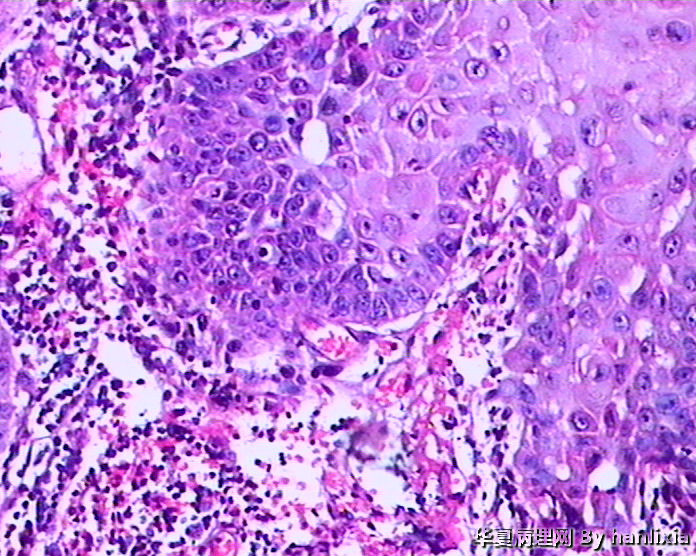

男性患者,50岁,发现面部皮肤(耳旁)肿物一年余,色黑。

部分区域突破基底膜,应该诊断鳞癌,由日光性角化发展过来的!

高分化鳞癌可能,也可能AK基础上发展而来的浅表型鳞癌?

高分化鳞状细胞癌

AK ,增生活跃,但好像scc不够?